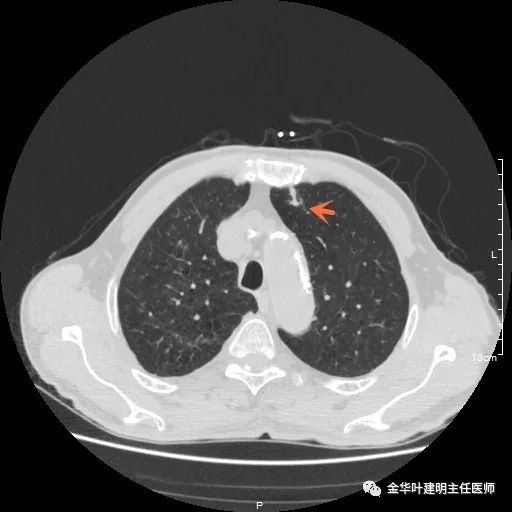

以上示右中叶病灶4。也是囊腔型病灶,病灶大,囊壁是磨玻璃密度,亦是较为典型的囊腔型肺癌影像。单病灶看,需中叶切除来治疗,因病灶3的存在,中叶切除可同时解决病灶3与病灶4。